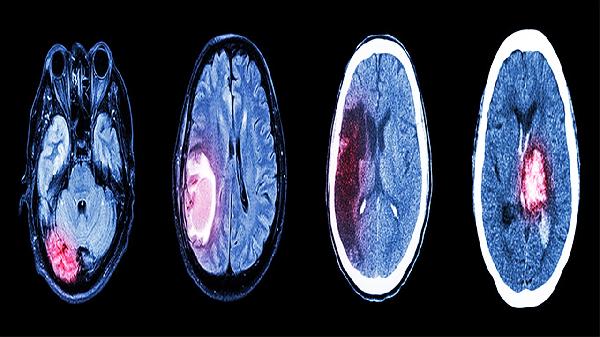

对于中风急性期出现的意识障碍或言语不利,牛黄与冰片协同可改善脑部微循环。临床多用于缺血性脑卒中伴意识模糊的辅助治疗,需与溶栓等西医手段联合应用。

现代研究表明牛黄能减少脑缺血再灌注损伤,对脑出血术后恢复期的神经功能修复可能有帮助。该作用需长期规范用药方能显现,急性期不可替代手术治疗。